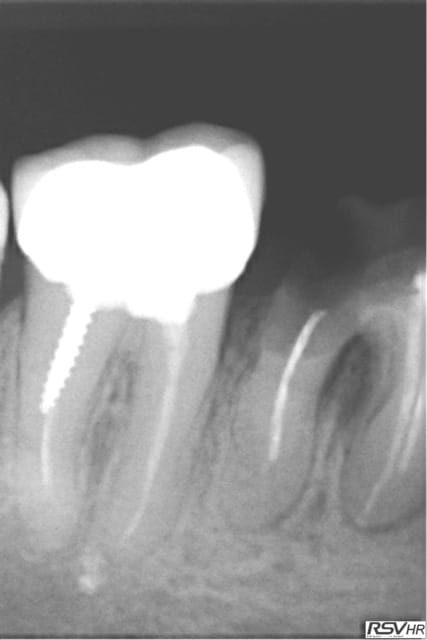

même si je me redirige plutôt vers Zimmer avec une insertion primaire supérieur (à mon avis ) voici un cas de plusieurs années

j'avais gardé une racine distale de 46 (montage 2 ccm soudées au début 4647- avec diastème avec 45 ;2008;le montage

n'a pas tenu longtemps=extraction racine distale et

implantation immédiate legacy2 7 mm(2011)

et ccm transvissée 3 mois après

radio à 2015